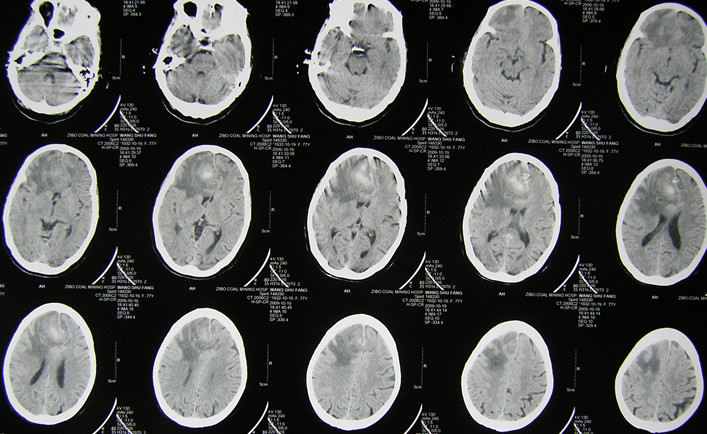

患者女,77岁,因突发头痛、恶心、呕吐并意识不清2小时急诊入院。无高血压病史。查体:浅昏迷状,右侧瞳孔4mm,光反应弱。CT示:右额叶高低密度灶,中线移位。诊断:右额叶脑卒中并脑疝早期。行急症开颅术。

术后2天CT复查:病灶清除良好,中线恢复。患者神志恢复,四肢活动良好。

术后3周CT复查:水肿消退,肿瘤清除彻底。患者已下床活动并出院康复,嘱其定期复查酌情放疗。